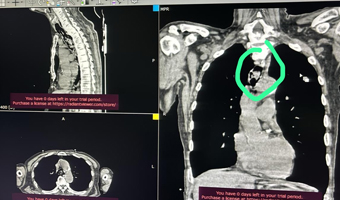

Nagamani and Sai Nath, parents from Proddatur, brought their 7-month-old baby to Shanthiram Hospital, concerned about severe bloating, abdominal swelling, and vomiting. Scans revealed a large mass in the baby’s abdomen (Retroperitoneal Tumor). Further tests showed that the baby had critically low hemoglobin levels (6.0),

prompting a blood transfusion before surgery could be performed. During the surgery, the baby’s blood pressure dropped, and the mass was found to be wrapped around vital organs, resembling cancerous growth. The mass was sent for further evaluation ie, histopathology and IHC evaluation, this would give us further direction of management in this child, currently, the child is relieved from the symptoms, further, the team will involve appropriate specialists for further medical management in this child if needed, stated Dr Ravinder leading the team

However, under the expert guidance of Pediatric Surgeon Dr. Ravinder, along with the anesthesia team led by Dr. Ravi Teja and Dr. Chiranjeevi, the retroperitoneal tumour surgery was completed. The mass was carefully removed without damaging surrounding organs, which the experts like the pediatric surgeon and the baby was safely discharged back home. The parents expressed their heartfelt gratitude to Dr. Ravinder, the anesthesia team, and the hospital management for giving their child a second chance at life.